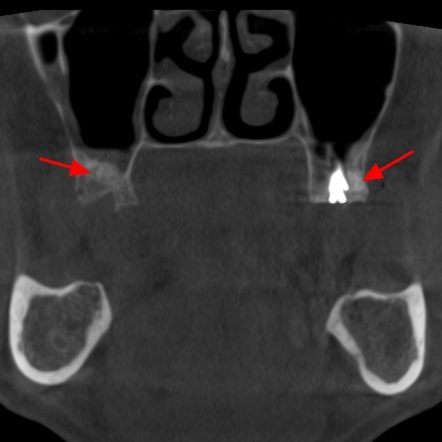

En este contexto, la tomografía computarizada de haz cónico (CBCT) se ha convertido en una herramienta esencial para los profesionales de la odontología. Gracias a la radiología 3D, los especialistas pueden evaluar con exactitud el volumen óseo disponible, identificar estructuras anatómicas importantes (como el nervio dentario o el seno maxilar) y diseñar el tratamiento con la máxima previsión y seguridad.

Para el paciente, esto se traduce en procedimientos más seguros, menos invasivos y con resultados más predecibles. En la fase de seguimiento, el CBCT también permite comprobar la correcta integración del injerto óseo y la evolución del tejido antes de colocar el implante definitivo.